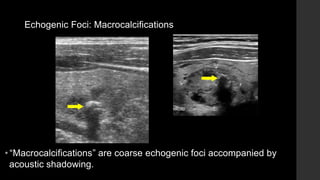

Echogenic Foci: Macrocalcifications

• “Macrocalcifications” are coarse echogenic foci accompanied by

acoustic shadowing.